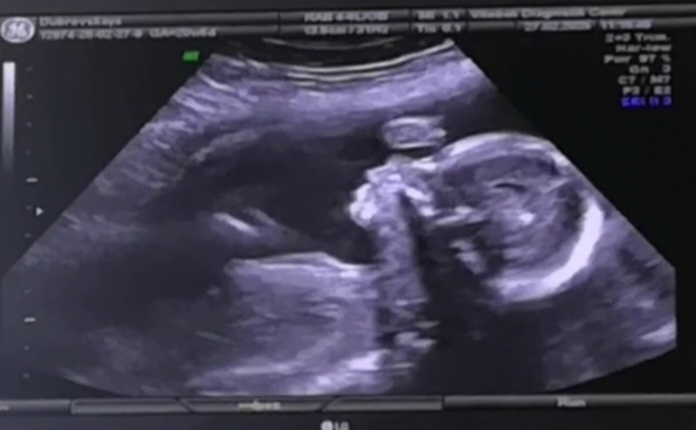

Вес 1900+-200г.(Сказала вес средний, мб чуть ниже среднего, будет аккуратненькой.Я так поняла, что опять мелкая в районе 3 кг). Лежит головой вниз.Ноги под попой сложила, тормошили, крутили, так и не показала пол, узистка сказала, что наверно тот, что и был на 2 скрининге.😂Будет сюрприз если поменялся.